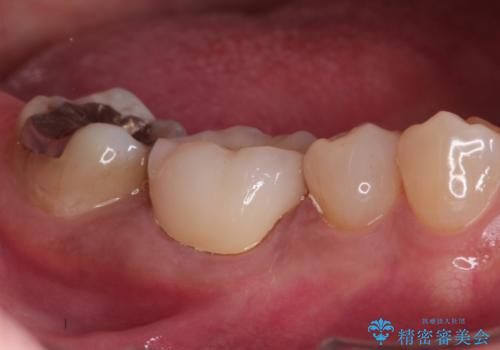

奥歯が痛い。精密根管治療〜オールセラミッククラウン

- 1週間前から冷たいもので強い持続痛を感じることを主訴に来院されました。

歯髄診断と痛みの再現により原因歯を特定し、症候性不可逆性歯髄炎の診断となりました。

根管治療〜オールセラミッククラウン(エクセレント)の治療を行なっております。

- 精密根管治療(イニシャルケース,大臼歯):122,000円、ファイバーコア:22,000円、仮歯:11,000円、オールセラミッククラウン(エクセレント):200,000円費用は治療当時の料金となります